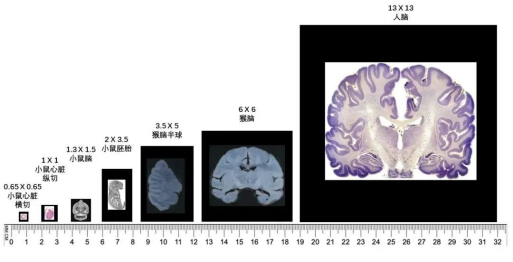

(2) 厘米级全景视场,检测组织大小可定制Stereo-seq技术设计的常规芯片大小为1 cm×1 cm,同时可根据组织大小定制不同尺寸的芯片。

(4) 物种组织不设限,人、动物及植物多覆盖Stereo-seq技术目前已研发了针对人、不同动物及植物的各部位组织器官的检测方法,完成了多种动植物的组织器官研究。